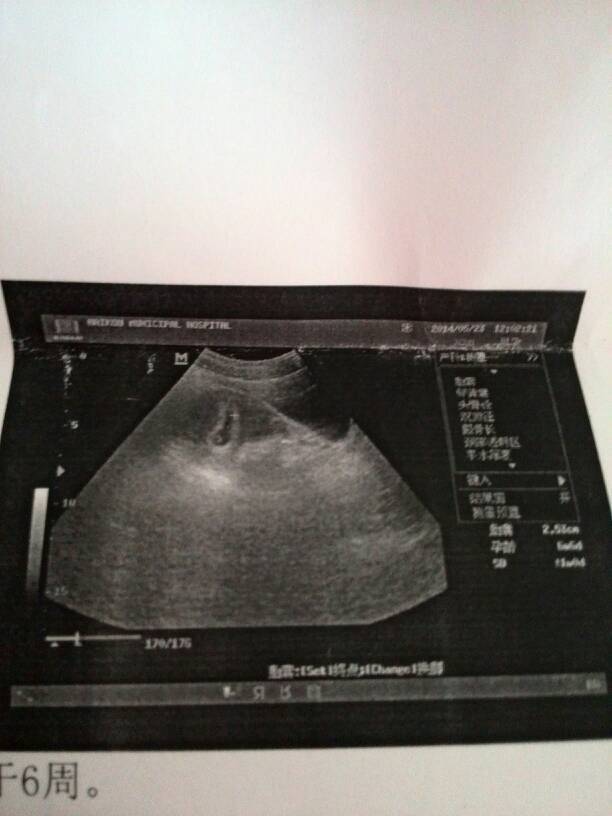

怀孕六周,腰两侧痛,无法入眠 去做B超,B超显示未见明显胚芽,这是什么意思?还有就是,B超从怀孕 怀孕六周,腰两侧痛,无法入眠。去做B超,B超显示未见明显胚芽,这是什么意思?还有就是,B超从怀孕到现在做了两次,对胎儿有影响吗?正常情况下应该做多少次,分别是什么时候?单子附上,感谢医生的回答! 点击展开 MINI小年糕 2014-05-23 13:13 为您推荐: 其他回答 问题分析: 您好 一般怀孕6周左右检查B超可见到胎囊。怀孕8周可见到有规律的胎心搏动。 意见建议:建议去正规医院按医师指导进行检查。 我的龙宝是吃货 2014-05-23 13:14 相关问题 怀孕6周,去医院做B超,医生说胚胎未见明显胚芽,这是什么状况? 怀孕七周多了做B超看不出胚芽及卵黄襄,血孕酮17 23,人绒毛膜促性激素1610 50,胎儿还能保 怀孕9周了,近来几天肚子有时候偶尔痛一下,其他没有其他不适五十六天的时候做的B超,一切正常,现在